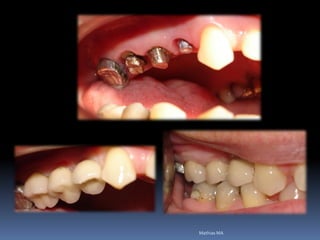

Reabilitação por implantes abre a visão de um

planejamento prévio, melhorando as condições da

área de trabalho antes da fixação por implantes

•Dentística/prótese

•Endodontia/periodontia

•Cirurgia/ortodontia

•Disfunções articulares